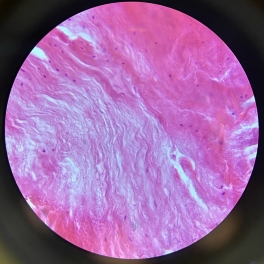

Dense Regular Collagenous Connective Tissue (Fibrous Tissue)

Dense Regular Elastic Connective Tissue (Elastic Tissue)

Smooth Muscle

Smooth Muscle

Smooth Muscle